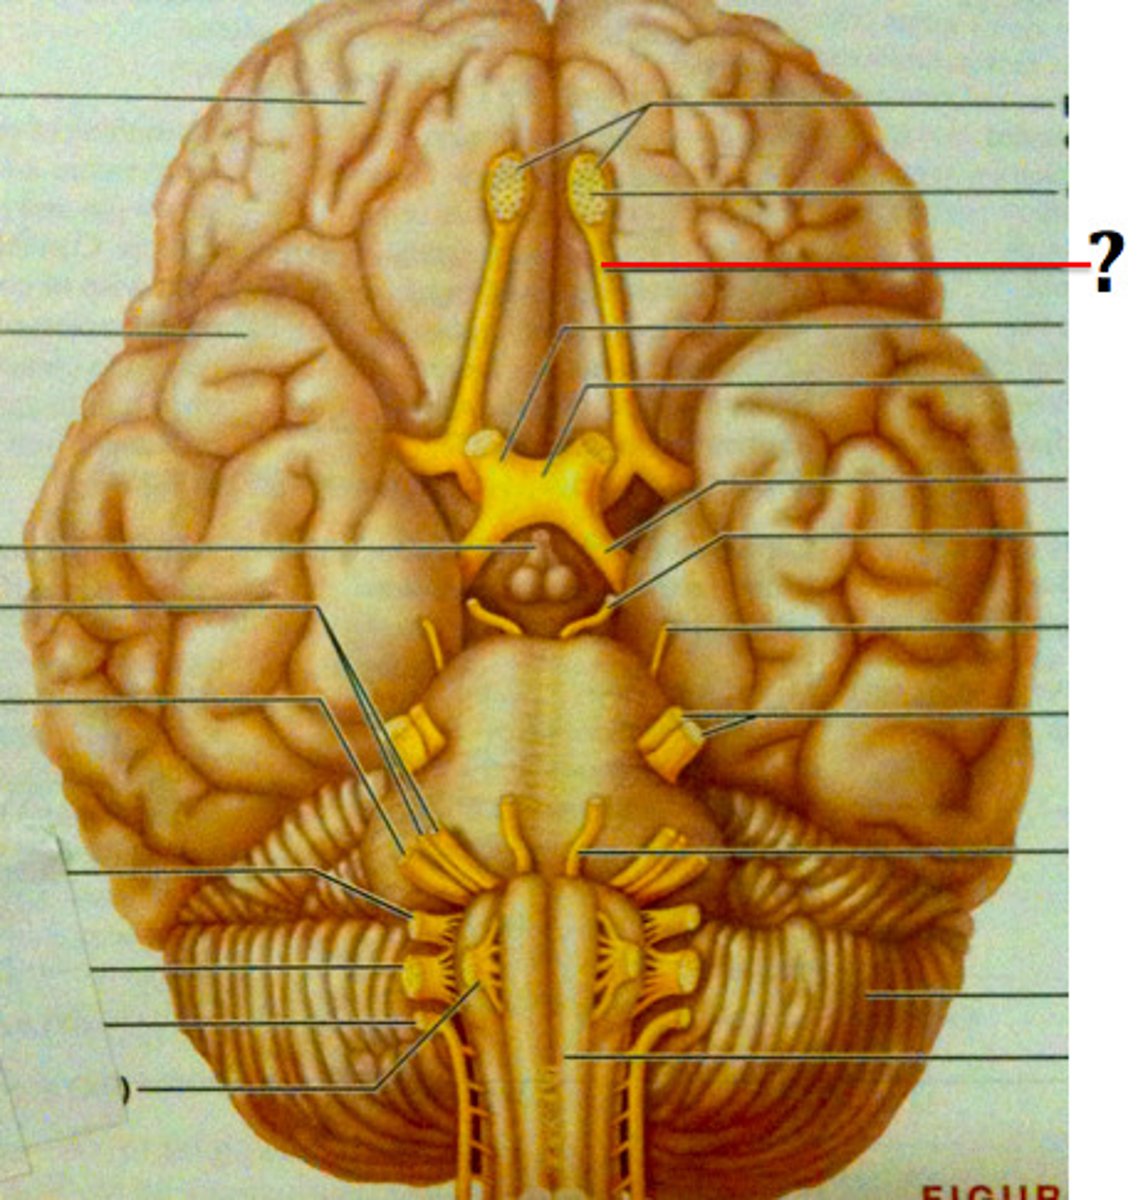

branches of olfactory nerve (cranial nerve I)

double check this

olfactory bulbs

olfactory tracts

optic nerves (cranial nerve II)

optic chiasma

optic tracts

CNIII (oculomotor nerve)

CNIV (trochlear nerve)

CNVI (abducens nerve)